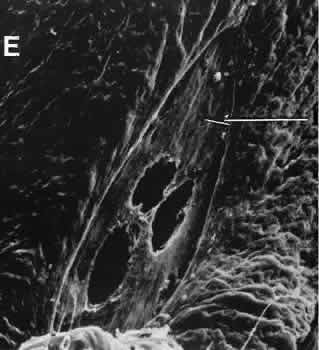

CATARACT EXTRACTION The cataract incision is made into the anterior chamber in such a way as not to injure the trabecular meshwork or unduly injure the cornea. The traditional cataract wound extends from the episcleral tissue posterior to the surgical limbus (defined by the insertion of the conjunctiva and Tenon's capsule) through the corneoscleral tissue to enter the anterior chamber by perforating Descemet's membrane anterior to Schwalbe's line. Clear corneal cataract incision involves only the peripheral cornea. Special circumstances may occur in which a more posterior or anterior route of incision may be desirable.55,56 The most reliable histologic landmark of a healed cataract incision (Fig. 14) is a hiatus of peripheral Descemet's membrane. The cut edges of Desce-met's membrane will curl inward toward the sclera.Endothelial cells may be absent or may have produced a new, thin, periodic acid-Schiff-positive Descemet's membrane over exposed corneal stroma. Occasionally, a fibrous plaque is present at the level of Descemet's membrane. This plaque is another example of fibrous metaplasia, in this instance of the corneal endothelial cells. The corneal stromal portion of the wound may be difficult to identify histologically, except in the early stages of healing. Clues to the position of the intrastromal tract include residual suture material, malorientation of collagen bundles, vascularization along the route of the incision, or incarceration of pigment, lens capsular remnants, or fragments of Descemet's membrane. The superficial portion of the wound tends to heal most completely. Breaks in Bowman's membrane will be present at the site of suture tracts and clear corneal cataract incisions. Also, areas of epithelial cell inclusion may be present in the substantia propria of the conjunctiva at the conjunctival incision. The capsulotomy incision is anterior to the insertion of the zonules through a relatively thick area of the anterior capsule. Most of the lens epithelial cells are removed with the anterior capsule, although some cells may remain in the region of the equator of the lens (Fig. 15). The residual lens capsule is thinnest at its posterior pole. The anterior capsular flap often adheres to the posterior capsule, encasing any residual cortical material and lens epithelial cells. Lens epithelial cells may grow to form large cells, called bladder cells, or may undergo fibrous metaplasia to form a collagenous plaque. Lens cortex outside the lens capsule has an amorphous appearance and is present only in the earliest postoperative specimens. Peripheral iridectomies are peripheral to the iris sphincter in the midportion of the iris rather than at the less accessible iris base. Complete or sector iridectomies include the iris sphincter but do not extend to the iris base. The edges of an iridectomy may show some rounding of contours, but granulation tissue does not form and iris pigment epithelial proliferation does not generally occur. The iris pigment epithelium may be absent for a considerable distance from an iridectomy produced by laser energy. Intraocular lens material (polymethylmethacrylate) often dissolves during tissue processing. Intraocular lenses containing metal components must be removed before embedding because metal will cause extensive artifacts and damage to microtome knives. Often the only clues to the presence of an intraocular lens are subtle compression changes of the iris or ciliary sulcus. Occasionally, residual synthetic material can be identified by polarized light. Anterior chamber lenses may cause a fibrous reaction in the anterior chamber angle (Fig. 16). Occasionally, collagenous tissue will completely encircle a lens (Fig. 17). Iris-supported lenses are associated with the loss of central iris pigment epithelium or residual nylon suture in the posterior chamber. Posterior chamber lenses are the most difficult to identify unless surrounded by lens remnants, in which case a negative image of the optic or loops can be seen. Sulcus-fixed lenses will show focal areas of iris pigment epithelial depigmentation or iris stromal erosion. The lens loop may displace the peripheral iris to come in contact with the trabecular meshwork. PENETRATING KERATOPLASTY Penetrating keratoplasty is a confusing term. The reference point of the incision is the globe; therefore, when a full-thickness graft is performed, the incision penetrates the globe but perforates the cornea. The concave-convex specimen usually is 7.0 to 8.5 mm in diameter and translucent because of fixation. Gross orientation of the specimen is important if pertinent changes are to be represented in the histologic section. Occasionally, as in keratoconus, the graft is placed axially and causes the pathologic area of thinning to be in an eccentric position in the graft. The area of the cone can be detected by observing the shadow of the specimen cast by a strong light. Descemet's membrane will not curl as extensively toward the stroma, as seen with in vivo wounds. Occasionally, Descemet's membrane is lost during tissue preparation because the membrane is easily sheared free of the corneal stroma. With repeat penetrating keratoplasty operations, the original corneal incision may or may not be represented in the specimen because of variations of size and position of the second graft procedure. Penetrating keratoplasty wounds in enucleation specimens can be identified by the changes in Descemet's membrane (Fig. 18). Because the donor tissue is often from a younger person, Descemet's membrane of the graft is thinner than the peripheral membrane of the host. Occasionally, redundant Descemet's membrane from the host intentionally will be left behind in this region by the surgeon. Often small areas of retrocorneal fibrous plaque mark the posterior area of the wound, even in cases of clinically uncomplicated wound healing. In time, the stromal portion of the wound may be undetectable histologically although some malorientation of the collagen lamellae often is present. Bowman's membrane does not reform as a distinct membranelike structure. Needle tracks or suture material may be seen in the tissue adjacent to the wound. Occasionally, epithelial cells may extend for a considerable distance along these suture tracks. REFRACTIVE SURGICAL PROCEDURES Laser in situ keratomileusis (LASIK) has become the predominant surgical procedure for the correction of refractive error, particularly myopia.57 An estimated 1.5 million LASIK procedures were performed in 2000.58 The advantages over previous laser procedures, particularly photorefractive keratectomy, include less postoperative pain, faster return of visual function, less regression of refractive effect, and less central corneal haze.58 The LASIK procedure provides access to the central corneal stroma with a mechanical oscillating steel microtome to create a lamellar flap. The microtome is stabilized to the anterior globe by a suction device that can raise the intraocular pressure to levels between 80 and 360 mm Hg, depending on the type of microtome used.59 The hinge of the flapmay be placed horizontally or vertically. An excimer laser removes a calculated amount of corneal stroma according to an algorithm determined for the type and amount of refractive error. The central corneal epithelium is not disturbed. The anterior corneal flap is repositioned without sutures. Central corneal thickness has become a critical fac-tor in determining the amount of tissue that can be safely removed to protect corneal endothelial cells. In most cases, the safety zone for the posterior cor-neal stroma has been established at 250 microns.60–63This zone is necessary to reduce the risk of endothelial cell damage and the risk of postoperative iatrogenic corneal ectasia.61 Several studies have shown a marked variation of normal central corneal thick-ness in a range of 472 to 651 m.64,65 The central corneal thickness is independent of axial length, age, sex, horizontal corneal diameter, and refractive error.64 Preoperative pachymetry is therefore mandatory. With several microkeratomes, scanning electron microscopy may show a fine undulating contour up to 0.2 mm at the border of the lamellar bed and flap. This feature is formed as chatter lines parallel to the cutting edge of the microkeratome blade (Fig. 19). The frequency of the chatter may relate to the nonlinear pass of the microkeratome. Chatter is absent in rotary keratomes and keratomes using a high oscillation frequency.66–68 The refractive outcome of all refractive procedures depends on the wound healing response of the corneal epithelium and stroma. The wound healing response in LASIK is found primarily at the region of epithelial transection at the edge of the flap. In animal models, epithelial reaction and production of type IV collagen is seen at the most peripheral edge of the lamellar flap. Gelatinase B, which is important in basement membrane remodeling, was localized to the basement membrane zone and superficial stroma.69 There is minimal to no inflammatory infiltrate along the margins of the lamellar bed. However, disorganization of the extracellular matrix extending to a depth of 5 μ from the surgical margin has been observed for as long as 9 months after surgery. The disorganization of the extracellular matrix suggests that the wound healing process is incomplete for a long period after surgery.70 Keratocytes in the region of the edge of the flap can be strongly stimulated by epithelial cell cytokines in part because of the localized absence of Bowman'smembrane. The potential for anterior stromal haze in the setting of LASIK is limited to the flap border, whereas in photorefractive keratectomy, the haze is most likely to occur centrally.71,72 In LASIK, there is a combination of intact corneal epithelium not producing cytokines and an intact Bowman's membrane limiting the diffusion of cytokines to influence underlying keratocytes.73,74 With LASIK, however, there appears to be increased interface reflectivity associated with thin lamellar flaps. There also appears to be a loss of keratocytes in the most anterior flap stroma in the period between 6 months and 2 years after surgery.75 Ophthalmic and maxillary branches of the trigeminal nerve supply the cornea. Most of the corneal stromal nerve supply is within the anterior two thirds of the stroma. Corneal sensation is essential for the maintenance of normal corneal physiology. The LASIK procedure transects nearly all corneal nerves except those located in the hinge of the flap. Corneal sensitivity is reduced 1 to 2 weeks after the LASIK procedure. The highest sensitivity is greatest at the hinge. Sensation has been noted to return during the next 6 months.76 Return of tensile strength to the lamellar incision of the corneal stroma is limited after LASIK. In an animal model, Maurice estimated that the wound healing process reestablished only 50% of the native tensile strength of the stroma.77 This lack of intrastromal adhesion is expressed in a rate of flap dislodgement estimated to be between 1% to 2% of LASIK procedures.78,79 GLAUCOMA SURGICAL PROCEDURES Laser trabeculoplasty causes distortion, shrinkage, and scarring of the collagenous beams of the trabecular meshwork. No perforation occurs into the area of Schlemm's canal. Cyclocryotherapy, cyclodiathermy (Fig. 20), and therapeutic ultrasonography apply energy directly to the pars plicata and cause lysis of the ciliary muscle and occlusion of the vascular supply, leading to extensive necrosis and scarring. Pressure lowering is accomplished by a reduction of aqueous production. Heat applied to the sclera may cause necrosis and localized scleral thinning. Cold applied to the sclera, unless extreme, does not cause any clinical or histologic changes. Cyclodialysis (Fig. 21) creates a cleft between the sclera and the longitudinal muscle of the ciliary body. Aqueous passes directly from the anterior chamber into the suprachoroidal space. Histologically, the longitudinal muscle of the ciliary body is disinserted from the scleral spur. Diaphanous tissue often is present in the suprachoroidal space along the route of filtration. The presence of this tissue differentiates the surgical site from artifactual disinsertion of the ciliary body, which is a common artifact of ocular tissue preparation. Many surgical variations are or have been used to create a fistulous tract between the anterior chamber and the episcleral tissue to allow continuous passage of aqueous from the eye. In most cases, the incision is placed at the surgical limbus or more posteriorly in the sclera. The primary variations center on ways to prevent the fistula from closing. Some older procedures simply used a large (2-mm) trephine hole, which was less likely to close than a smaller opening. Cautery placed at the exposed edges of the sclera causes retraction of the wound edge to maintain the fistula. In trabeculectomy, a half-thickness window of posterior peripheral cornea is excised to create a large internal orifice for a fistulous track under a protective scleral flap. Iridencleisis intentionally includes incarceration of iris into the wound to prevent complete scleral healing. Multiple types of foreign material, from horsehair to gold to silicone, in solid or tubular forms, have been fashioned into setons to maintain the opening to the anterior chamber. Some varieties of the setons route aqueous to the equator of the eye, where it is resorbed by the surrounding tissue. Most recently, various agents have been used to control the rate and extent of fibrous proliferation in a surgical fistula. Currently, the most common agent is mitomycin-C, although 5 fluorouracil has been used in the past.80,81 The exact mechanism of action is not known, but limitation of proliferation and migration of cells involved in the wound healing process appears to play a substantial role.82,83 Trabeculectomy specimens usually consist of a tiny portion of pigmented and translucent tissue. The translucent tissue, representing the posterior peripheral cornea, should be oriented perpendicular to the limbus to show Descemet's membrane and any possible trabecular meshwork. Occasionally, clinically unsuspected epithelial ingrowth or neovascular channels may be found (Fig. 22). The neovascular channels can be differentiated from native vessels by their thin adventitial sheaths. RETINAL REATTACHMENT Evidence of previous retinal reattachment surgery is most commonly shown by synthetic bands and other surgical devices on the surface of an enucleated globe. Occasionally, the episcleral fibrous tissue reaction completely encases these materials in a fibrous cloak. The bands and other materials are easily identified after sectioning the globe. The internal signs of surgery include indentation of the sclera and regions of uveal and retinal pigment epithelial depigmentation caused by cryotherapy. The retina may or may not be attached. The synthetic bands are partially soluble in organic solvents used in tissue dehydration for paraffin embedding. The negative image of the material can be seen, usually in the equatorial region, surrounded by a variable degree of fibrous tissue and focal collections of chronic nongranulomatous inflammatory cells (Fig. 23). Occasionally, a foreign body granulomatous reaction is present near degenerating suture. Often the uveal tract in the area of surgery is completely atrophic, as is the overlying retina. Frequently, the retinal pigment epithelium has become depigmented and areas of fibrous metaplasia may be present. Glial proliferation and chorioretinal adhesion may be seen in areas of cryotherapy or diathermy.84,85 Laser photocoagulation of the retina at therapeutic energy levels results in a chorioretinal adhesion between proliferating Müller cells and retinal pigment epithelial cells or between the glial component and the denuded inner surface of Bruch's membrane. The internal limiting membrane of the retina, the basement membrane of the retinal blood vessels, and Bruch's membrane remain intact. Numerous focal areas of choriocapillaris defects remain in the area of photocoagulation. |